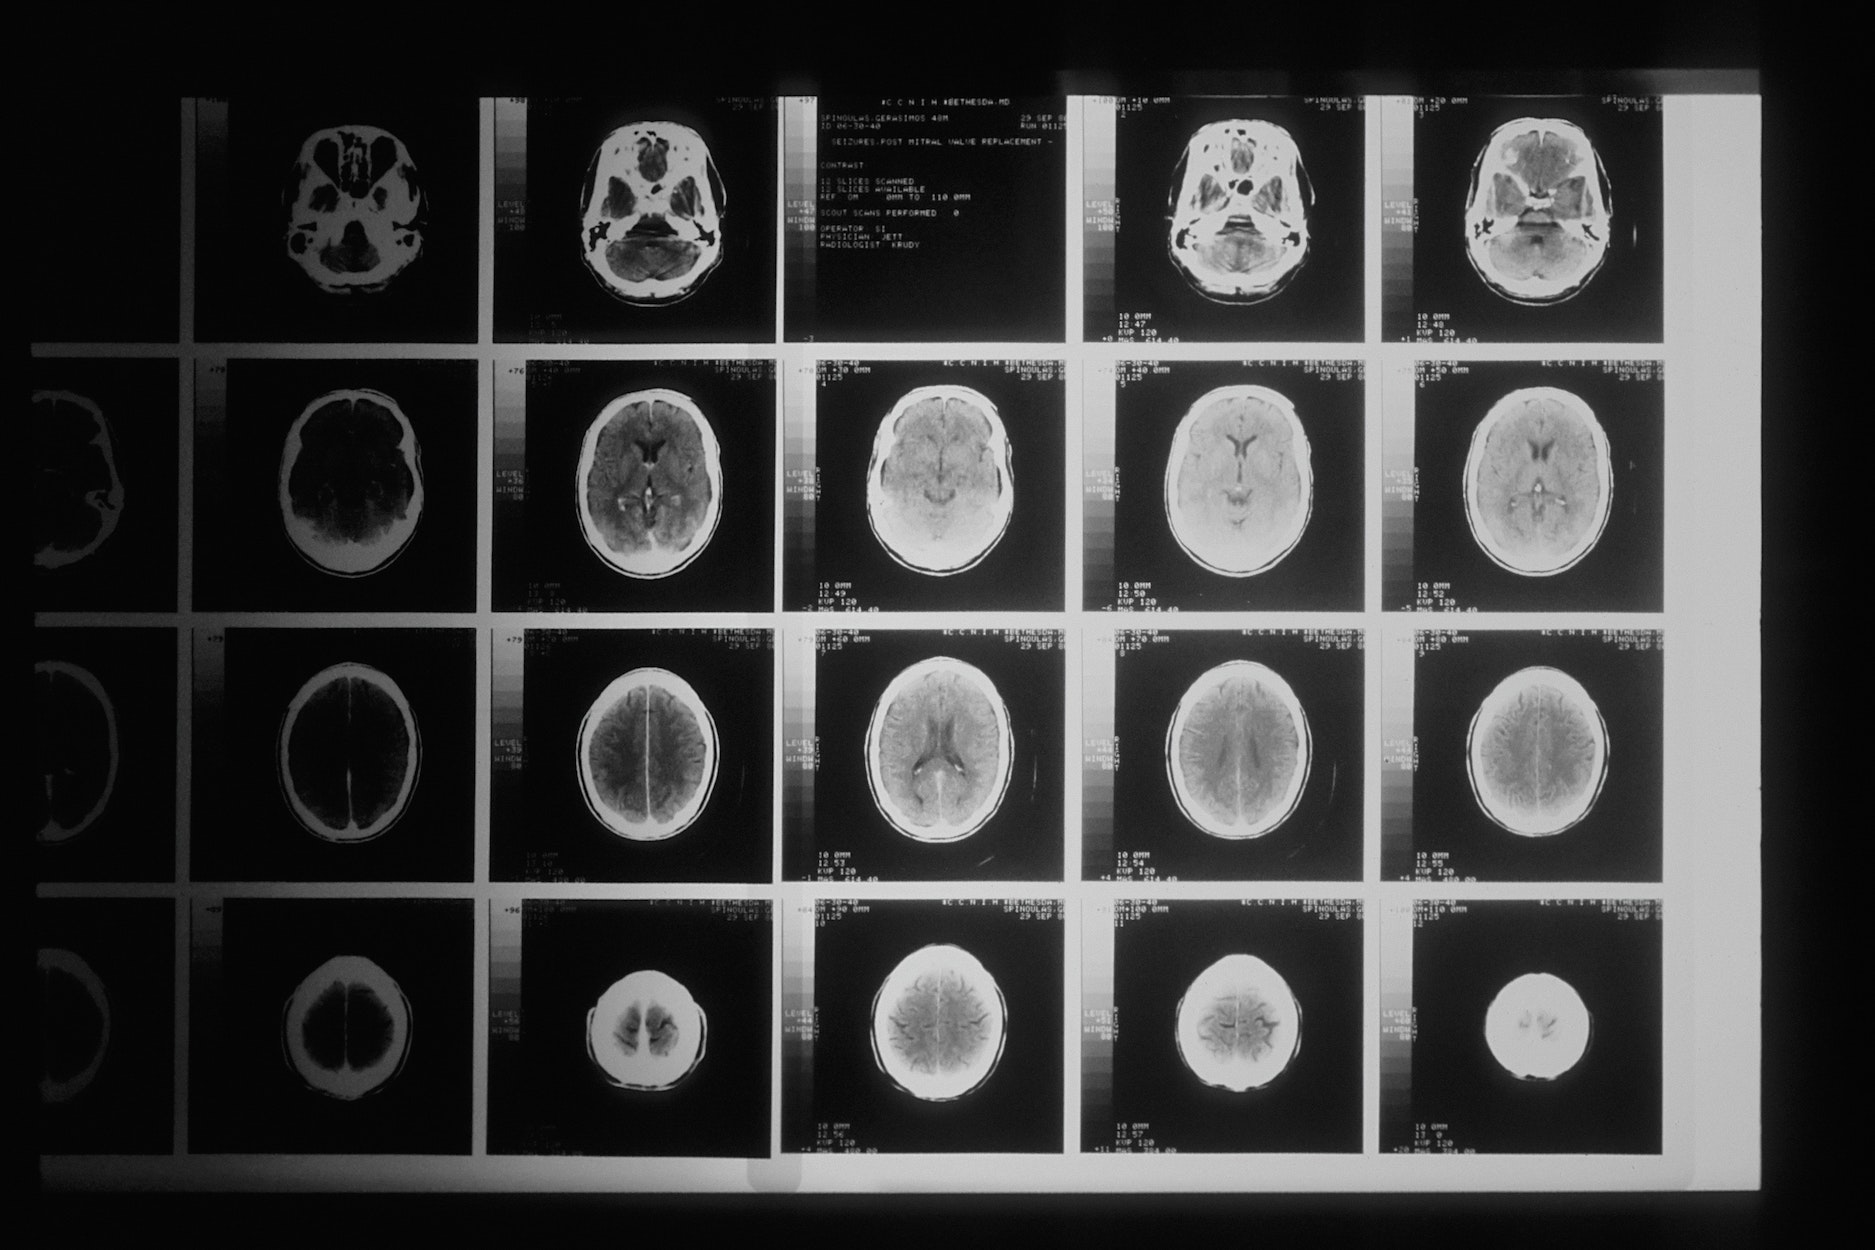

Does a Normal CT or MRI Rule Out a TBI?

The CDC’s mild TBI and concussion overview explains that a brain scan is not required to diagnose a mild TBI, and imaging is often used to look for dangerous complications rather than “prove” a concussion. Merck Manual’s concussion guide notes that CT and MRI results are usually normal in concussion, so symptom history and exam details matter.

- Normal scan: does not automatically mean normal brain function

- What matters: consistent symptoms, exams, and follow-up notes

- Better proof: testing that measures attention, memory, balance, or vision

- Risk issue: scans can still be urgent if red-flag symptoms appear

Insurance adjusters often lean hard on “normal imaging” because it sounds simple, even when the day-to-day function story is not simple at all. That is what we mean by leverage when we build a record that shows consistent complaints, consistent care, and objective testing instead of debating one scan report.